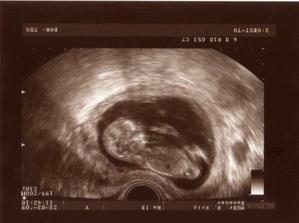

Sofinka je na světě

Dne 30.9.2009 se nám narodilo naše očekávané sluníčko - naše Sofinka (3,70kg a 51cm). Rodila jsem v porodinici v Benešově a vše bylo na jedničku.